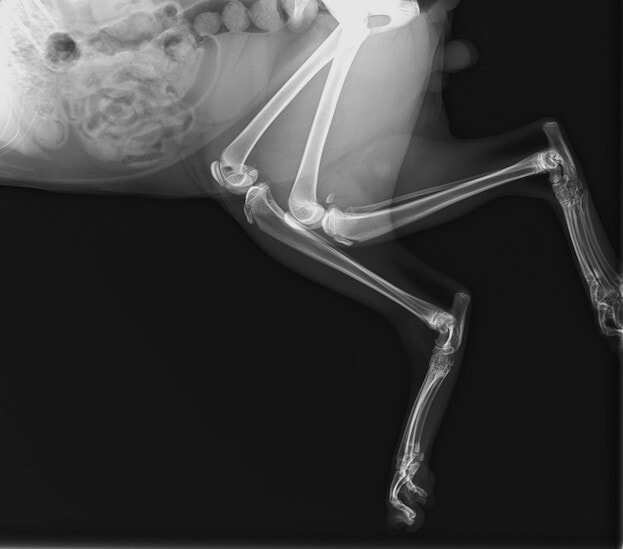

症例3:キルシュナーワイヤーのピンニングによる整復

ペルシャ猫 11ヶ月齢 雄

他院にて左大腿骨遠位の成長板骨折(salter-harrisⅠ型)が認められており、治療相談を目的として来院。当院にて、キルシュナーワイヤーを用いたピンニングにより骨折部位の整復を行いました。術後の経過は良好で、現在も経過観察中です。

術前レントゲン